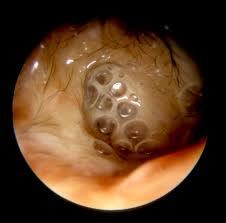

Question 3

Question

Describe the disease shown in this picture!

4615f4aa-cdbe-427c-bcf0-c88cc7d8b3d5 (image/jpg)

Answer

Direct contact between keratinizing squamous epithelium in external meatus and mucoperiosteum of middle ear damaged by inflammation

Tx: Remove matrix, perimatrix, eroded bone

Can progress to labryinthitis, meningitis , brain abscess

Fetid otorrhea, purulent

No perforation is observed